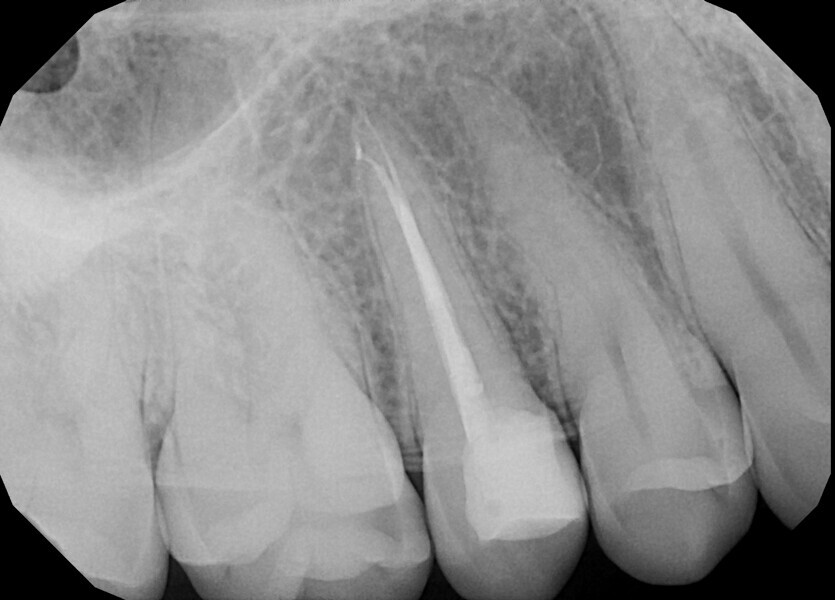

Case 4

The patient was referred to Dr Karaś’s office for non-surgical root canal retreatment of tooth #46. The tooth was symptomatic, and the radiographic examination revealed a periapical lesion around the mesial root. The periapical lesion was clearly visible, but the shape of the root canal was not clear (Fig. 22). The examination was extended by CBCT imaging. The CBCT scan revealed internal resorption in the mesiobuccal canal and an isthmus and apical inflammatory root resorption in the apical area of the mesial root (Fig. 23). A cast post and prosthetic crown were also noted.

Two treatment plans were presented to the patient, non-surgical root canal retreatment and surgical root canal retreatment. After intra-oral examination, the quality of the prosthodontic treatment was found to doubtful (Fig. 24). The decision was made to remove the crown and perform non-surgical retreatment.

After local anaesthesia, the crown was cut with a high-speed handpiece (Fig. 25). The post was exposed and removed (Fig. 26 & 27). The pulp chamber and root canal orifices were examined for cracks. After inspection, a gingivectomy was performed (Fig. 28) and a dental dam (Kerr Dental) was placed (Fig. 29). The dental dam was sealed with a temporary flowable material (Fig. 30). After sealing the dental dam, the full adhesion protocol with a sixth-generation self-adhesive primer and bonding agent was performed, and the pre-endodontic build-up was created (Fig. 31). Residues of the cement and root canal filling materials were removed with a diamond-coated ultrasonic tip (Woodpecker; Fig. 32). Patency was easily established with hand files (VDW), and the canals were shaped with rotary martensitic files (Poldent) up to 40/0.04. Each step of instrumentation was performed with lubricating cream containing EDTA (VDW; Fig. 33). After each instrument, the canals were flushed with 5.25% sodium hypochlorite (Cerkamed). After reaching the final sizes of the root canals, the irrigation protocol was performed: three sequences of 5.25% sodium hypochlorite and 40.00% citric acid (Cerkamed) activated with an ultrasonic file (MANI), followed by 5.25% sodium hypochlorite activated with the ultrasonic file for approximately 10 minutes (Figs. 34 & 35). The flow of the liquid between both mesial canals was visible.

At this stage, one of the most important decisions had to be made regarding the resorption and isthmus present in the mesial root. On the one hand, in the case of non-penetrating internal resorption, the material of choice is gutta-percha with a sealer. On the other hand, in the case of apical inflammatory root resorption, it is recommended to use mineral trioxide aggregate (MTA) or putty materials. There is no problem with using these two materials in the same root in most cases, but in this case, the canals were too narrow to use the MTA comfortably and the quality of filling of the isthmus that could be achieved was questionable.

From this point of view, a novel approach of placing a tricalcium silicate-based sealer was a promising idea. The sealer was placed in the previously described manner. The premixed sealer in the plastic syringe (Meta Biomed) was placed in the mesiobuccal canal and the syringe depressed until it filled the mesiolingual canal. The distal canal was filled separately. In each canal, pistons from the previously heated gutta-percha extruder were placed and the warm gutta-percha was slightly compacted with stainless-steel hand condensers. A periapical radiograph was taken to evaluate the quality of the obturation. The bioceramic sealer was slightly extruded through the resorbed apex into the periapical area (Fig. 36). After the obturation, the chamber and orifices were cleaned (Fig. 37). A resin core with fibre posts was placed, and the temporary pink material was removed. The patient was referred to the prosthodontist for final restoration.

The recall appointment was performed after three years. The periapical radiograph and CBCT scan revealed healing of the periapical tissue and no resorption of the bioceramic sealer (Fig. 38). The tooth remained asymptomatic.